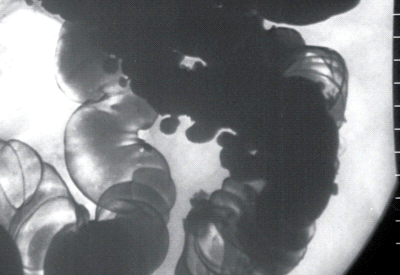

Рис. 2 Иригоскопия:

неосложненный дивертикулез сигмовидной кишки.

Наиболее информативным методом

выявления дивертикулеза толстой кишки является исследование толстой кишки с

помощью бариевой клизмы (ирригоскопия). При неосложненном дивертикулезе

кишечная стенка имеет неровный контур и образует мешковидные выпячивания по ее

контуру, имеющие суженное основание (устье). Размеры этих выпячиваний

колеблются от 0,2-0,3 до 1-2 см, чаще в сигмовидной и нисходящей ободочной

кишках. Для выявления дивертикулов иногда необходимы снимки в боковой проекции.